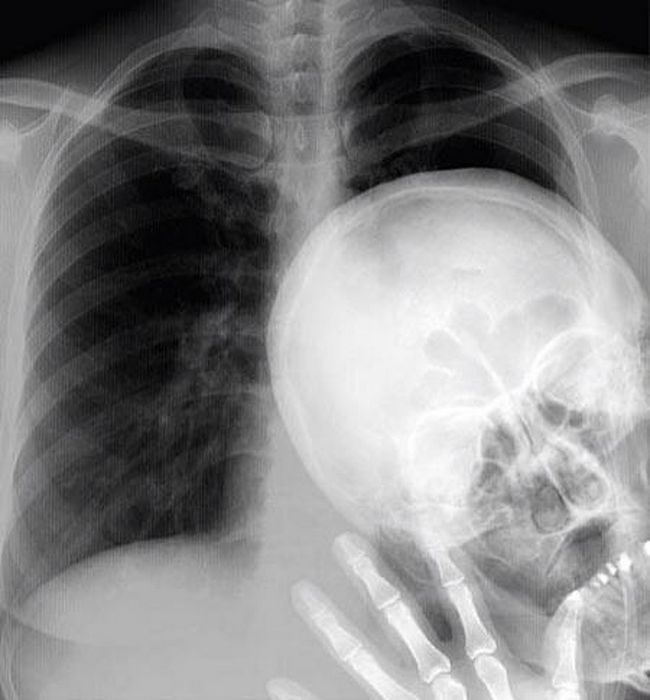

7 – Photobomb no raio X